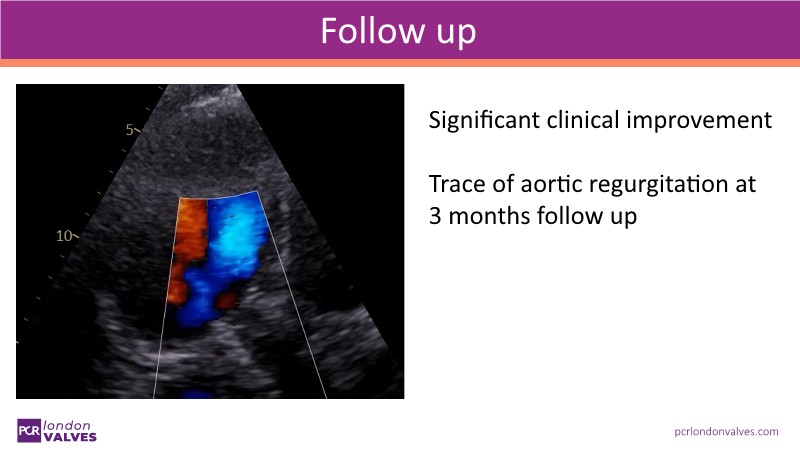

This session examines the evolving treatment landscape for aortic regurgitation (AR) in light of new ESC guidelines and dedicated devices such as the JenaValve Trilogy System. It provides an in-depth look at refined diagnosis, optimized treatment strategies, and presents real-world data and clinical cases that highlight the commercial performance and efficacy of the Trilogy System in Europe.